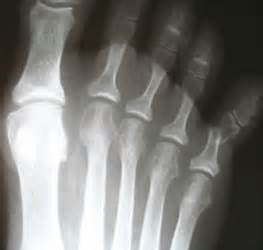

第五腳趾骨折...最常見的腳的腳趾骨折 中壢高正雄骨科復健診所